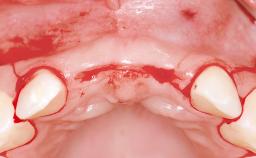

In 2001, a 48-year-old woman presented at a dental clinic with a failing fixed partial denture spanning from teeth 13 to 21. She was experiencing pain upon function, tenderness to palpation facial to tooth 13, and severe mobility of the prosthesis. Radiographic and clinical assessment revealed a subcrestal fracture of tooth 13, making its restoration unlikely. It was determined by the clinician that the tooth needed to be extracted prior to proceeding any further with dental care. After the extraction, the patient lost confidence in the progression of her treatment and sought consultation at the Center for Implant Dentistry. At her consultation visit in our clinic, an extra- and intraoral clinical examination revealed a medium lip line at full smile and an edentulous area spanning from 13 to 12 with both vertical and horizontal deficits in hard and soft tissue.

Soft Tissue Anatomy Intact Defective

Bone Volume Horizontally and vertically sufficient Horizontally deficient Deficient vertically or deficient vertically AND horizontally